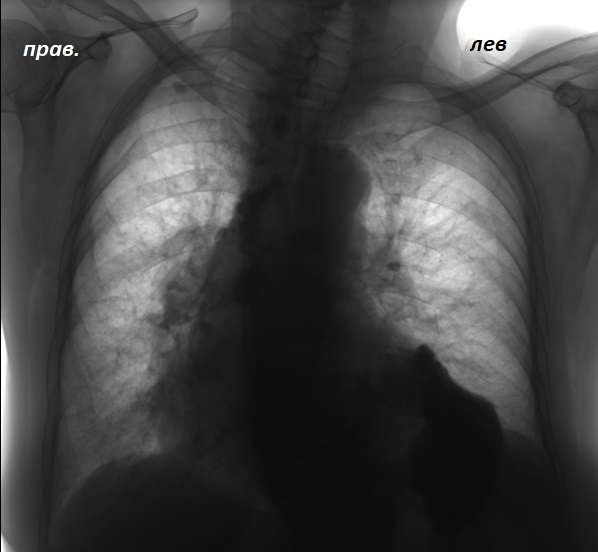

Фотографии, демонстрирующие обнаруженное усиление легочного рисунка

Раздел: Фотодневник открытий